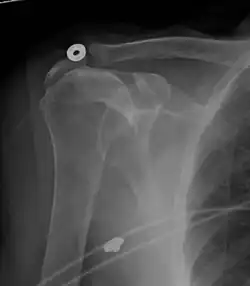

MRI

MRI of normal shoulder intratendinous signal

MRI of rotator cuff full-thickness tear

Magnetic resonance imaging (MRI) and ultrasound[46] are comparable in efficacy and helpful in diagnosis, although both have a false positive rate of 15–20%.[47] MRI can reliably detect most full-thickness tears, although very small pinpoint tears may be missed. In such situations, an MRI combined with an injection of contrast material, an MR-arthrogram, may help to confirm the diagnosis. It should be realized that a normal MRI cannot fully rule out a small tear (a false negative) while partial-thickness tears are not as reliably detected.[48] While MRI is sensitive in identifying tendon degeneration (tendinopathy), it may not reliably distinguish between a degenerative tendon and a partially torn tendon. Again, magnetic resonance arthrography can improve the differentiation.[48] An overall sensitivity of 91% (9% false negative rate) has been reported, indicating that magnetic resonance arthrography is reliable in the detection of partial-thickness rotator cuff tears.[48] However, its routine use is not advised, since it involves entering the joint with a needle, with the potential risk of infection. Consequently, the test is reserved for cases in which the diagnosis remains unclear.